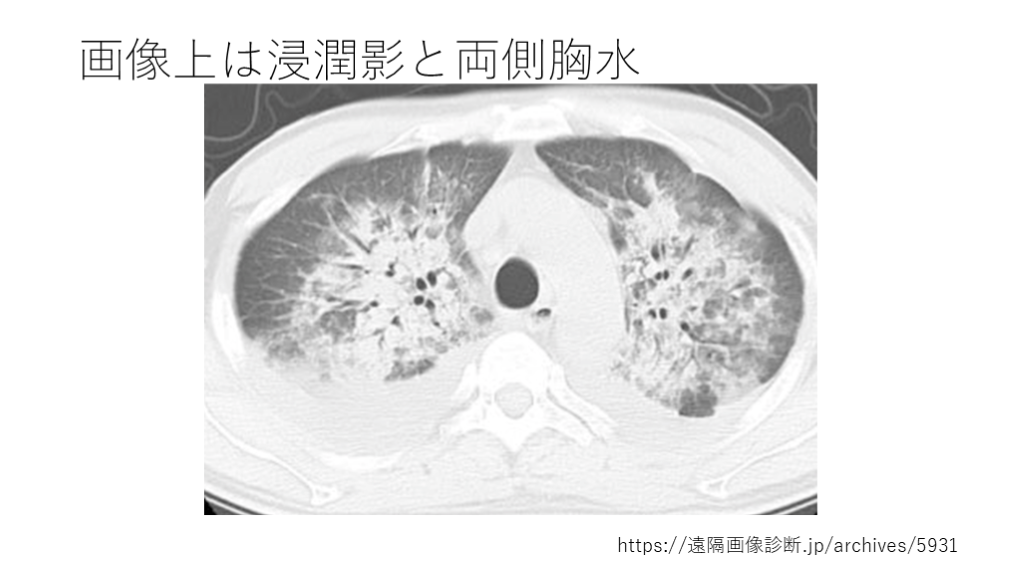

https://遠隔画像診断.jp/archives/5931 中枢側では血管が集中し、間質が豊富 胸膜直下はリンパ流や間質構造が 違い、sparingしやすい